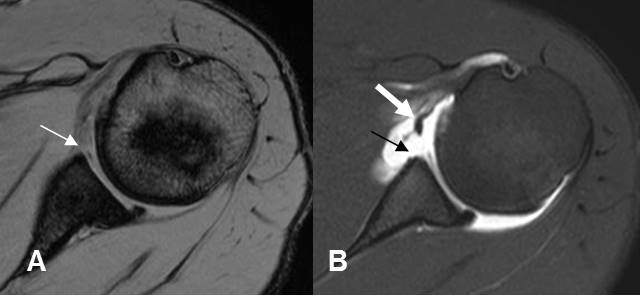

Fig 171. Lesión de Bankart.

A: RM axial en FFE y B: ArtroRM axial. Signos de lesión de Bankart, que se confirma en la ArtroRM. (Flecha delgada). Adicionalmente hay ruptura del LGH medio. (Flecha gruesa).